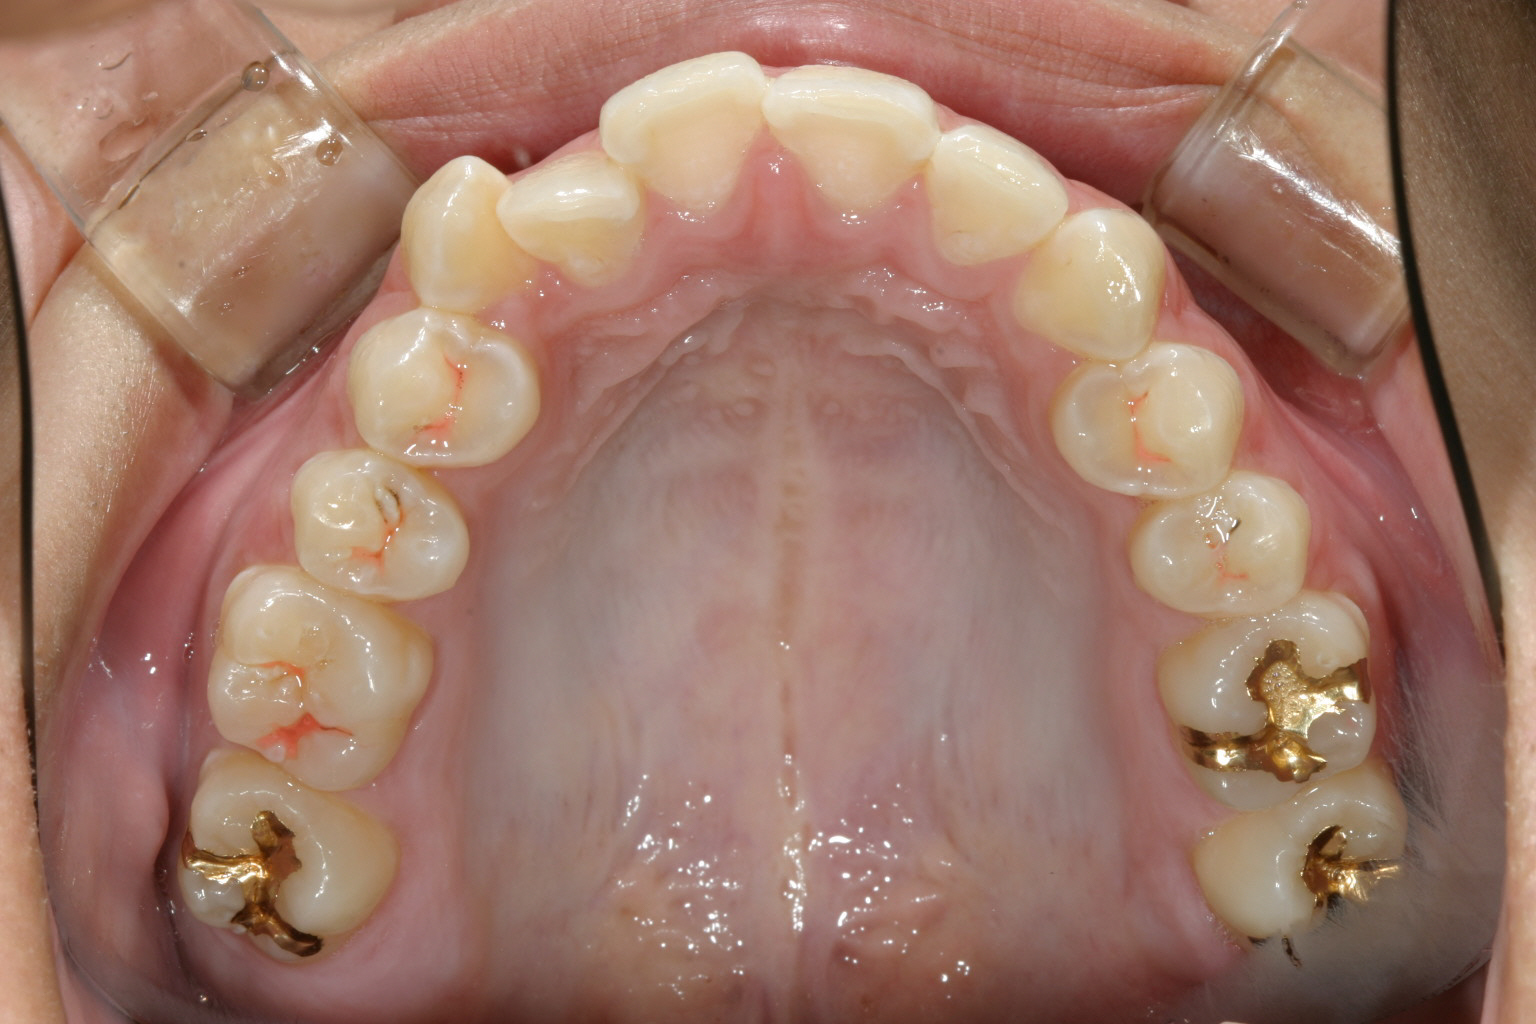

インプラントとワイヤーとバネの力を利用して右側臼歯を遠心移動してるのが分ります。

上にインプラントとワイヤーとバネです。 下はマルチループです。

写真上部にインプラントが見えます。

特に難儀したのが右上の奥歯の位置関係が悪く、先ずは右上の親知らずを抜歯してそこに奥歯を順番に後ろへ送っていくと言う手順です。そう言うふうにする事により飛び出した犬歯をアーチに乗せると言う事が可能になりますが手間のかかる仕事でした。